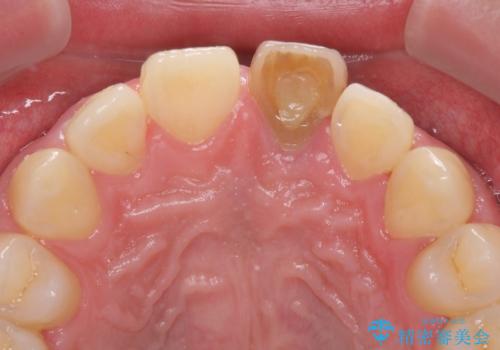

- 中学生の時にぶつけて以来、そのままにしていたところ前歯が変色してきたとのことで来院された患者様です。

レントゲン写真より、歯の中の神経組織が失活していることが分かったため、根管治療、ファイバーコアによる土台築製を行い、オーダーメイドタイプのオールセラミッククラウンにて補綴することとしました。